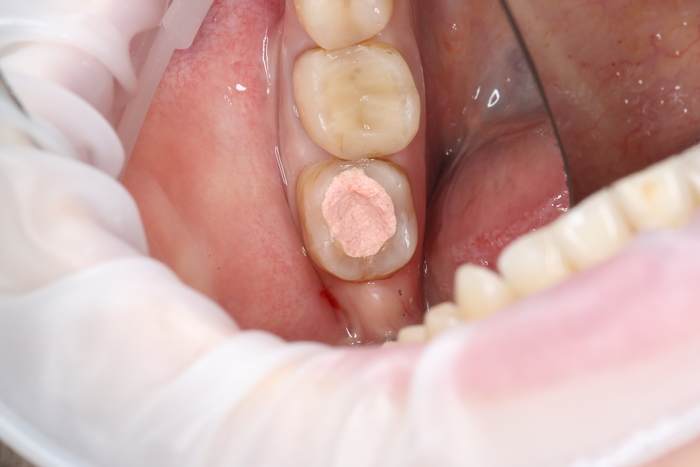

После снятия коронки:

Выкрутили абатмент:

Установлена заглушка, которая закрывает шахту имплантата.

Теперь необходимо выждать около 2-х месяцев для того, чтобы десна восстановилась (Пациентка это время ходила со специальной капой, которая имитирует наличие зуба).